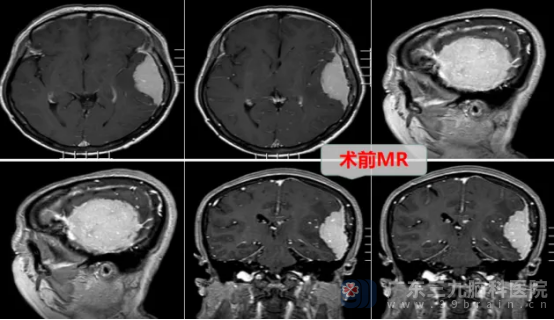

入院时,患者的言语仍偶有混乱。我院神经外十科专家为患者完善相关检查后,发现患者的左侧额颞顶部颅骨内板下占位侵犯邻近颅骨,范围约78mm×26mm×66mm,周围脑叶水肿且可疑受累,占位血供丰富,怀疑是不典型脑膜瘤可能性极大。

面对挑战,神经外十科团队迅速集结,深入研讨,审慎评估,制定周密手术方案。排除手术禁忌后,1月10日,一场与病魔的攻坚战打响。神经外十科学术带头人欧阳辉教授和副主任林德留带领医疗团队,凭借精湛技艺与丰富经验,如精细的工匠,在错综复杂的脑部组织间,小心分离肿瘤,全力守护正常组织,最终成功全切拳头大小的肿瘤。手术顺利完成。术后病理为脑膜皮细胞型脑膜瘤,CNS WHO1级,属于良性肿瘤。